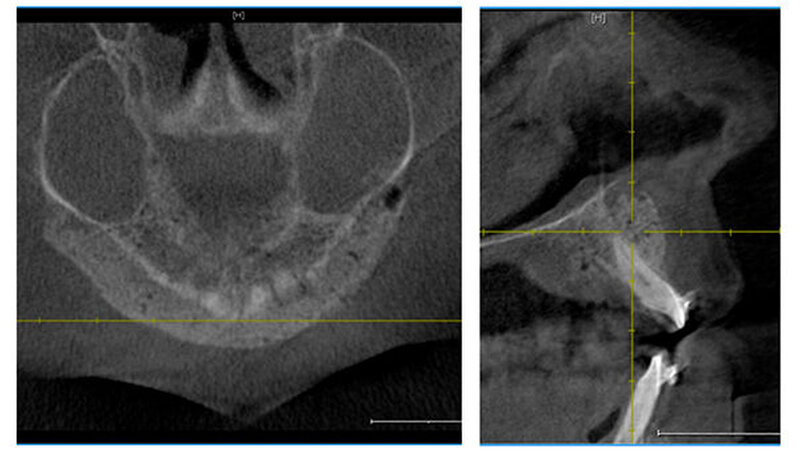

Heute, nach zirka eineinhalb Jahren, zeigt sich die Patientin mit der funktionellen und ästhetischen Verbesserung durch die operativen Eingriffe äußerst zufrieden. Sie befindet sich weiterhin in engmaschiger zahnärztlicher/kieferorthopädischer Kontrolle sowie in regelmäßigen Zeitabständen in kieferchirurgischer Nachsorge (Abbildungen 2a bis c).